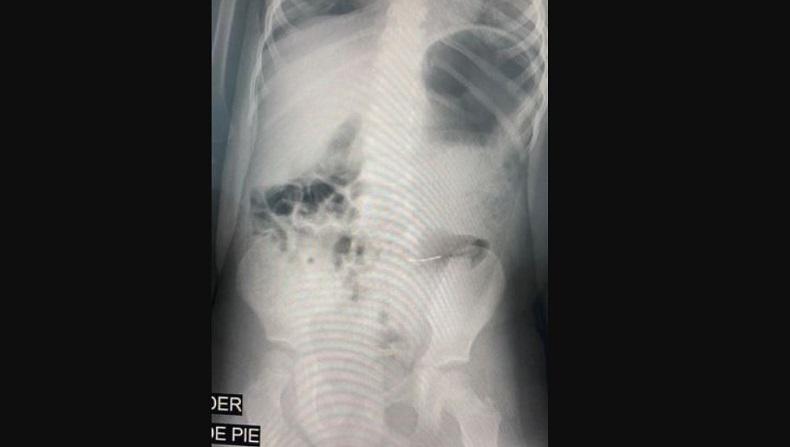

Dalam perut bocah di Meksiko, terdapat logam yang tampak saat difoto menggunakan sinar-X. (Foto: CEN)

Maria Fernanda dan saudara perempuannya Renata, dirawat di rumah sakit setelah pesta ulang tahun di Kota Monterrey, negara bagian Nuevo Leon, Meksiko. Dalam perut mereka terdapat logam yang tampak saat difoto menggunakan sinar-X.